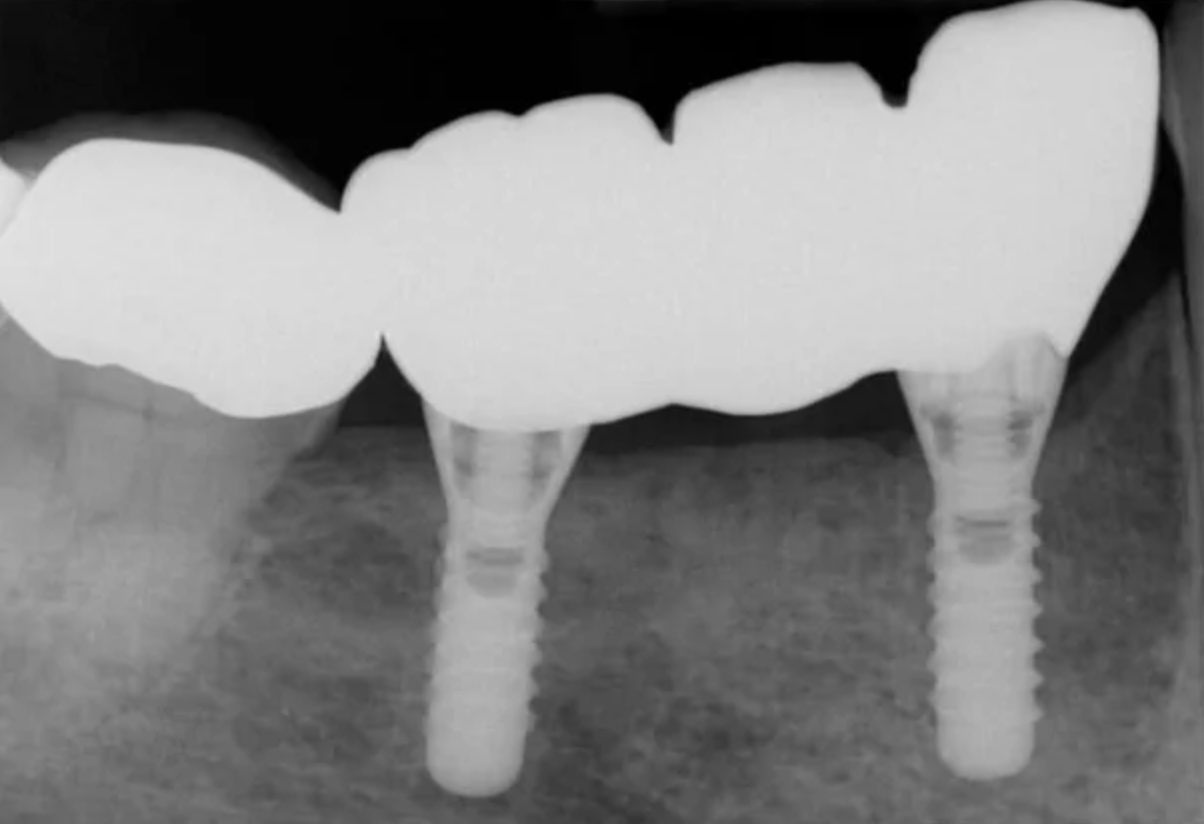

Open tray screw retained impression copings were then attached and confirmed with radiographs, and a three-unit veneered zirconia bridge was constructed using Variobase lab cemented abutments to provide an all-in-one screw-retained restoration.

The definitive restoration was then inserted and checked for passivity of fit. The abutment screws were then definitively torqued to 35 Ncm. The access cavities were restored with PTFE tape and composite resin.